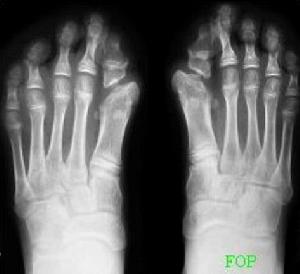

為該病最早的特徵表現,幾乎所有的患者都會發生。手足畸形為指(趾)骨短小。拇趾較拇指為多見,有的表現為一節指骨(趾骨)的缺如,或二趾間融合變短,也可見掌骨和近節趾骨骨性聯合。

凡每一個病例均有對稱性拇指(或拇趾)畸形,對診斷本病很有幫助。

X 線片顯示腫物的軟組織當中有分散鈣化影。過一段時間,急性期的症狀和體徵消失後,腫物變小,鈣化影也縮小,但密度增高。X線片上可見柱狀或不規則形態的團塊狀不同密度的骨化陰影,可與骨骼相連,也可完全游離。骨骼呈現失用性萎縮。